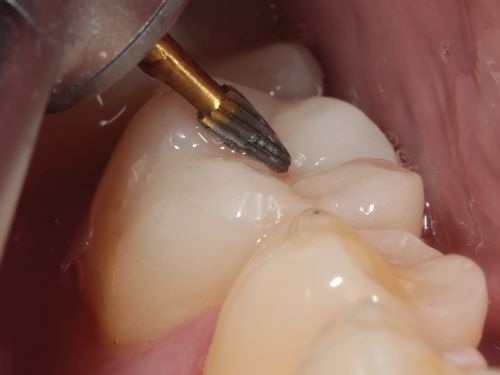

A 35-year-old male presented to the clinic to replace some inadequate restorations, one of which was for the lower right first molar (Fig. 1). For this tooth, the molar was restored with composite resin using the direct technique. The operative field was isolated, the old restoration was removed, and surface hybridization was completed using Futurabond U universal adhesive from Voco (Fig. 2). After placing a sectional matrix and a spacer ring, the composite resin (Voco’s GrandioSO 4U, shade A2) was placed in the proximal box with a thickness less than 4 mm, which is the maximum recommended thickness for the chosen material (Fig. 3). Additional increments of composite resin were applied to complete the anatomical stratification. The final morphology was sculpted, followed by light-curing to ensure complete polymerization (Fig. 4). The rubber dam was removed (Fig. 5), and the occlusion was adjusted using a finishing carbide bur with 12 blades (Fig. 6). Finishing and polishing was completed, with the final result shown in the Figures 7 and 8.

Fig. 6